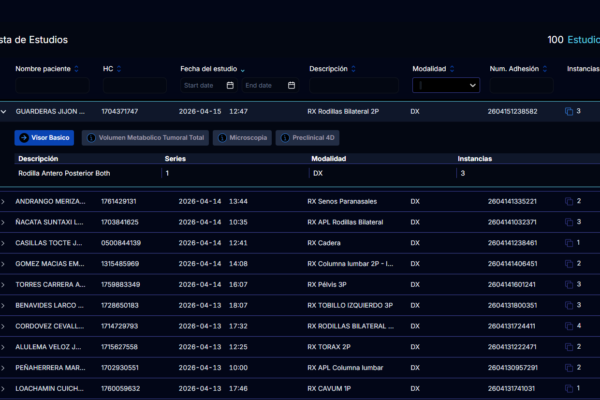

El LIS gestiona el flujo completo del laboratorio clínico, desde la recepción de muestras hasta la entrega de resultados al paciente y al médico tratante.

- Recepción de muestras: Registro, etiquetado, trazabilidad

- Órdenes de laboratorio: Perfiles de exámenes, pruebas individuales